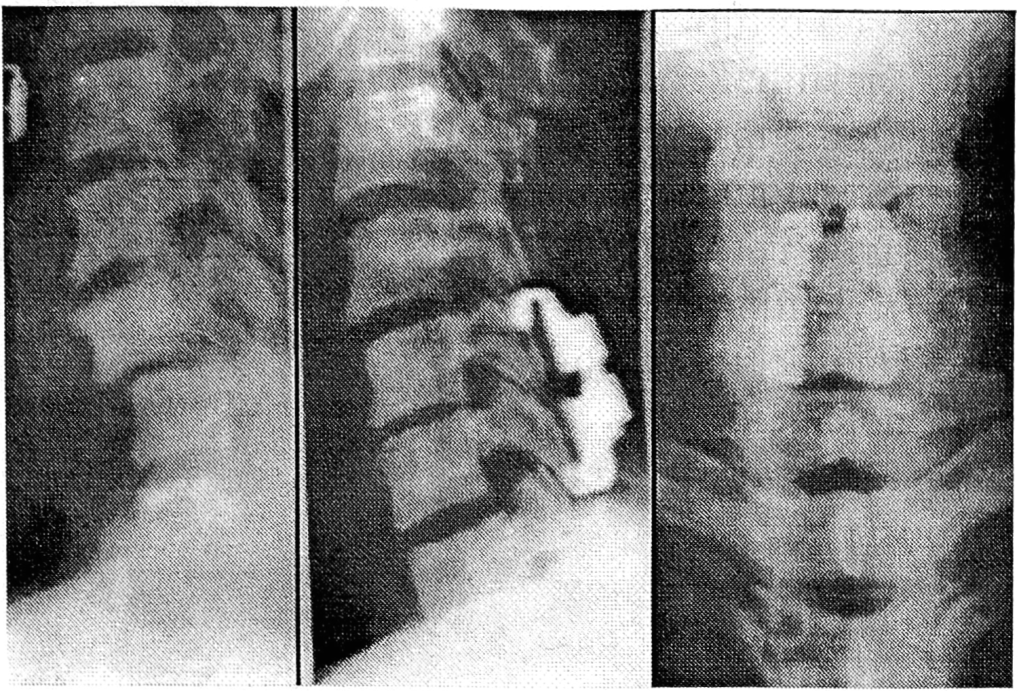

Следует отметить, что использование диамагнитных титановых конструкций позволяло выполнять КТ и МРТ и в послеоперационном периоде с минимальными артефактами, не имеющими существенного значения для визуализации состояния позвоночного канала и спинного мозга (рис. 4).

Рис. 4. Магнитно- резонансная томограмма позвоночника и спинного мозга после транспедикулярной фиксации конструкциями фирмы «Медбиотех».

Оперативные вмешательства проводились с учетом вида и локализации поражения, характера стеноза позвоночного канала и сдавления спинного мозга и его корешков, подтвержденных миелографией, КТ и МРТ. У 24 больных произведены репозиционно-стабилизирующие операции с необходимой интраоперационной коррекцией деформации. В 86 случаях выполнены декомпрессивно-стабилизирующие вмешательства — гемиламинэктомия (12), ламинэктомия (47) или заднебоковая декомпрессия (27) с последующей интраоперационной многоплоскостной коррекцией и фиксацией пораженного сегмента. Выраженная нестабильность повреждения и сохраняющийся стеноз позвоночного канала со сдавлением спинного мозга и его корешков, подтвержденные в послеоперационном периоде миелографией, КТ и МРТ, явились показанием к передней декомпрессии и спондилодезу, выполненным вторым этапом у 10 больных (рис. 5).

Рис. 5. Рентгенограммы позвоночника больного с переломовывихом L1—2 позвонков до и после двухэтапного лечения с применением транспедикулярного фиксатора «Медбиотех».